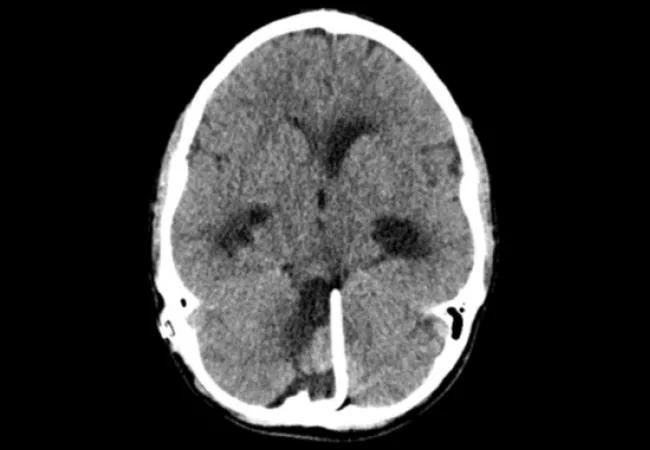

With this information we embarked on a systematic treatment plan (see Figure 1) that included removal of his complex shunt system (due to infection) and placement of three separate external ventricular drains, each of which was systematically tested for dependency (after the infection cleared) independent of the others.

Figure 1. Preoperative (top row) and postoperative (bottom row) imaging studies of the case patient. Top: Left image shows the supratentorial bilateral ventricular shunt system (right frontal and left occipital) in florid failure at presentation. Middle image shows the infratentorial fourth ventricular shunt. Radiograph on the right shows the triple shunt system. Bottom: Left image shows the bilateral frontal ventricular peritoneal shunts postoperatively, with acute hydrocephalus resolved. Middle image shows successful weaning of the fourth ventricular catheter. Radiograph on the right shows the simplified two-catheter system.